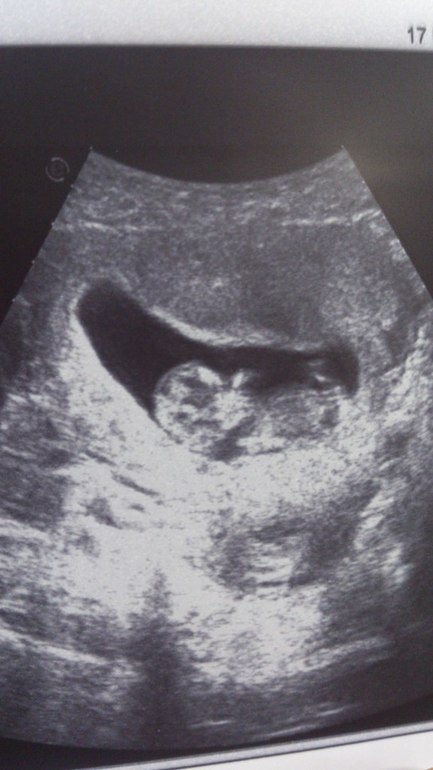

Скрининг первого триместра =)

По УЗИ она мне срок поставила 11 недель и 2 дня, а по последним месячным у меня получается 11 недель и 3 дня, отлично прям.

Никаких отслоек и прочего, ттт, нет. Есть киста жёлтого тела в левом яичнике, но она должна рассосаться сама, а пока сказали тяжестей не поднимать и не напрягаться лишнего, вот.

А еще мне даже фотку распечатали =)) Люблю я нашу ЖК, прям приятные там все (кроме терапевта, кстати).